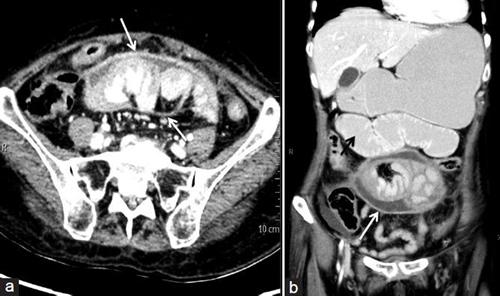

得了腹茧症怎么办?

第一:去了医院,我跟医生说我的情况之后,医生带我去做了B超,发现我的肠管被中午粘连,在X线钡餐检查中也发现小肠受压,医生说这是肠梗阻,是腹茧症的表现,需要做手术